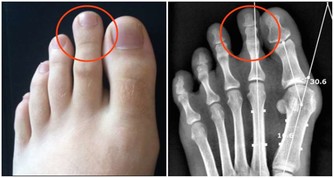

肺臟排毒

蘿蔔是肺臟的排毒食品:在中醫眼中,大腸和肺的關係最密切,肺排出毒素程度取決於大腸是否通暢,蘿蔔能幫助大腸排泄宿便,生吃或拌成冷盤都可以。

百合提高肺臟抗毒能力:肺臟向來不喜歡燥氣,在燥的情況下,容易導致積累毒素。蘑菇、百合有很好的養肺滋陰的功效,可以幫肺臟抗擊毒素,食用時加工時間不要過長,否則百合中的汁液會減少,防毒效果要大打折扣。